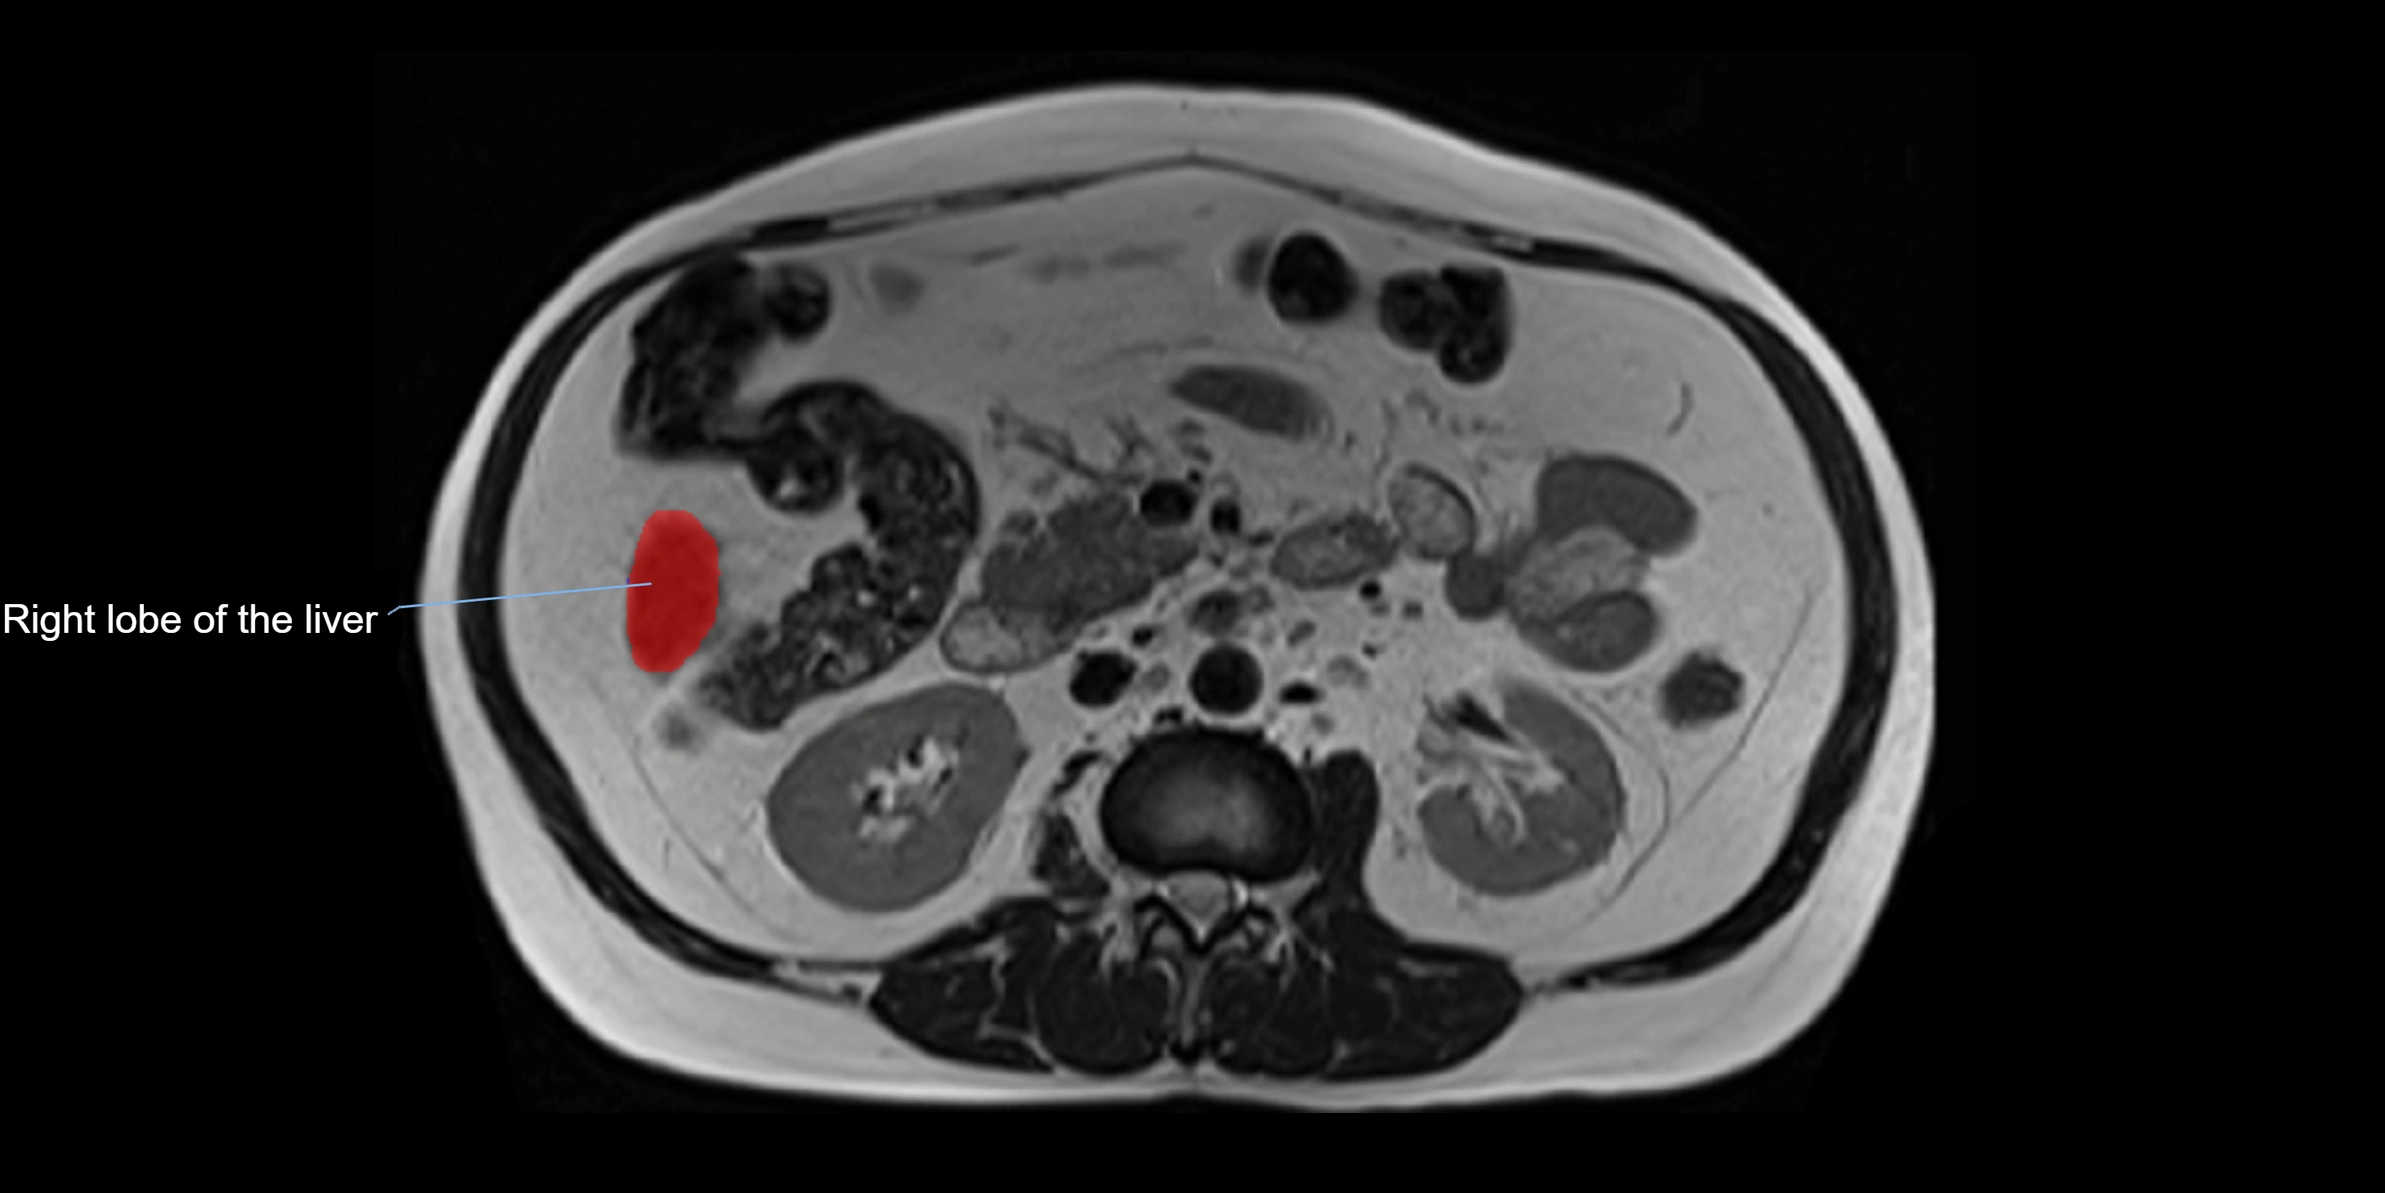

The caudate lobe of the liver is a distinct anatomical subdivision of the liver, designated as segment I in Couinaud’s classification. It lies on the posterior surface of the liver, between the fissure for the ligamentum venosum (left boundary) and the groove for the inferior vena cava (IVC) (right boundary). Superiorly, it is related to the posterior liver surface, and inferiorly it is separated from the left lobe by the porta hepatis.

This anatomical autonomy makes the caudate lobe especially significant in liver surgery, transplantation, and hepatic venous outflow obstruction syndromes (e.g., Budd–Chiari syndrome). Enlargement of the caudate lobe is a characteristic imaging feature in chronic liver disease and cirrhosis.

• Enlargement may be appreciated in cirrhosis or Budd–Chiari syndrome